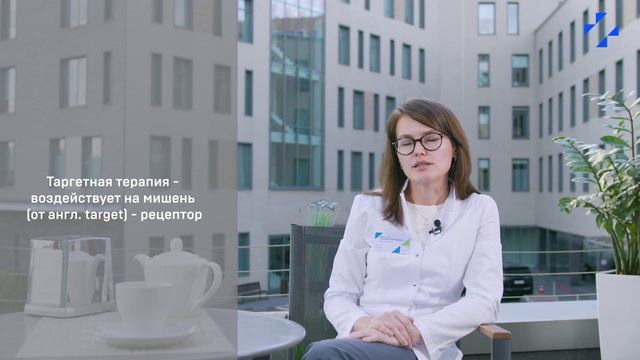

Таргетная терапия РМЖ: Инновации в лечении

Раздел: Кадры-подсказки